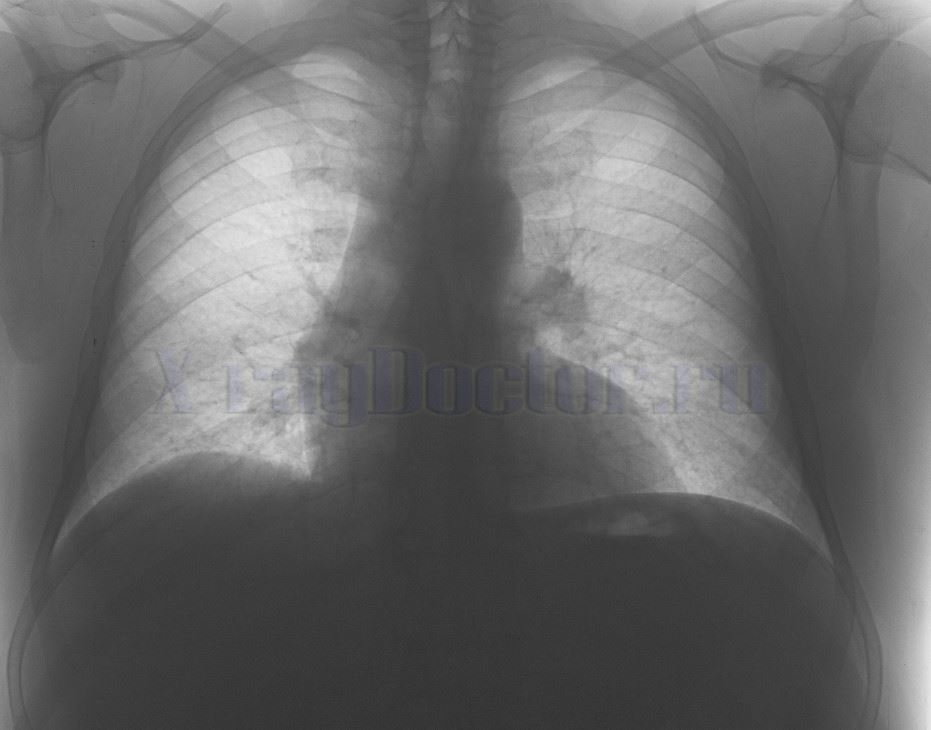

Что видно на снимке легких при воспалении бронхов:

- пластинчатые или очаговые ателектазы (очаги спадения ткани);

- небольшие участки инфильтрации;

- изменения сосудистого рисунка, который напоминает «ветки дерева»;

- участки повышенной пневматизации на легочном рисунке: крупные сосуды прослеживаются, а мелкие исчезают.

Чтобы определить на снимке обструктивный бронхит, следует изучить рентген-симптомы изменения бронхиального дерева:

- Расплывчатость корней.

- Снижение структурности.

- Нечеткость контуров сосудов.

- Изменение и усиление легочного рисунка.

- Утолщение бронхиальных стенок («симптом трамвайных рельсов»).

Дополнительные признаки патологии на рентгеновском снимке формируются обструктивным синдромом:

- увеличение прозрачности легочных полей при повышении вентиляции альвеол;

- сглаженность куполов диафрагмы;

- вертикальное расположение сердечной тени;

- проявление гипертензии по малому кругу;

- ограничение подвижности куполов диафрагмы (при рентгеноскопическом исследовании).

Запущенные случаи воспаления бронхов сопровождаются дополнительными синдромами на снимках органов грудной клетки:

- Выраженное нарушение хода легочного рисунка.

- Появление участков с отсутствием сосудов.

- Обнаружение полостей (бронхоэктазов, булл).

- Увеличение общего просвета бронхов.

- Сужение просвета артерий.

- Появление локальных очагов уплотнений.